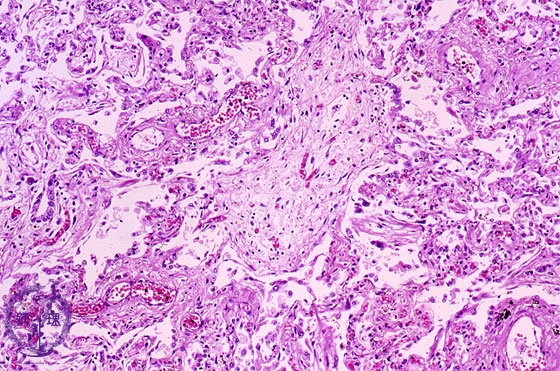

Microscopic view (HE stain, intermediate power view): Within the affected bronchiolar lumen, polypoid granulation tissue (Masson body, dotted line) is seen.